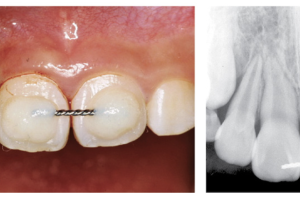

Средний возраст полного прорезывания третьих моляров - 20 лет, хотя у некоторых пациентов процесс может продолжаться до 25 лет. При нормальном развитии третьи моляры сначала занимают горизонтальное положение, но с развитием корней и ростом челюсти угол наклона меняется от горизонтального к мезиоангулярному, а затем к вертикальному положению. Нарушение поворота и изменения положения из мезиоангулярного к вертикальному является наиболее частой причиной ретенции третьих моляров. Второй значимой причиной является несоответствие мезиодистального размера зуба по отношению к длине челюсти и недостаточное количество имеющегося места альвеолярной части нижней челюсти перед ветвью для полноценного прорезывания.

Как упоминалось выше, у некоторых людей, в особенности у лиц женского пола, третьи моляры продолжают прорезываться после 20 лет, достигая своего окончательного положения к 25 годам. С продолжающимся прорезыванием связаны различные факторы. При позднем прорезывании ретенированные зубы обычно покрыты только мягкими тканями или незначительным количеством костной ткани. Такие зубы обычно расположены вертикально и находятся достаточно поверхностно относительно окклюзионной поверхности рядом расположенного второго моляра, а завершение формирования корней таких зубов происходит достаточно поздно.

Наконец, и, наверное, наиболее важным аспектом для прорезывания третьего моляра является достаточное количество места между дистальной поверхностью второго моляра и передним краем ветви нижней челюсти. Данный причинный фактор ретенции третьих моляров наиболее наглядно проявляется в исследовании, где большая часть ретенированных зубов прорезывалась, хоть и обычно они располагались более мезиально, если во время развития третьего моляра происходила потеря соседнего второго моляра. Аналогично, если нижний третий моляр не прорезывается после 20 лет, то скорее всего он покрыт костной тканью. К тому же, чаще всего зуб расположен мезиоангулярно и расположен в альвеолярном отростке ниже уровня шейки соседнего второго моляра. По этой причине стоматологи для предварительной оценки могут использовать данные параметры и спрогнозировать, прорежется ли зуб или останется ретенированным.